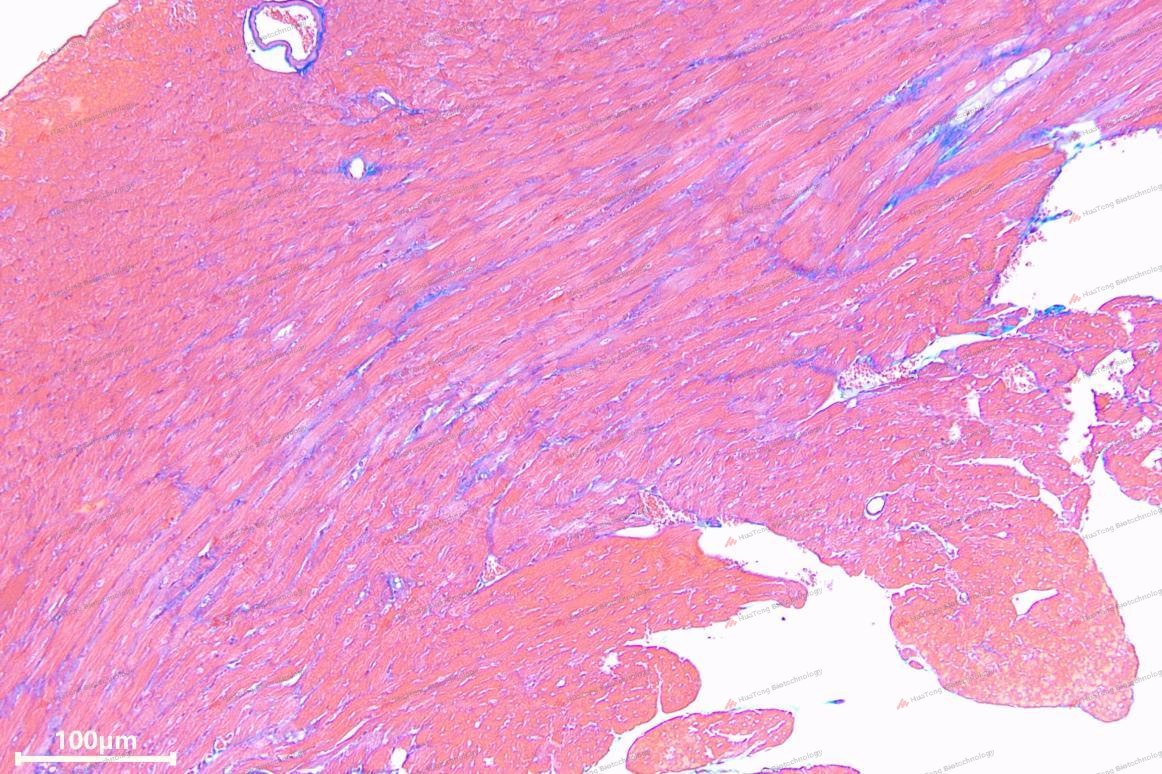

• Histology: Wheat Germ Agglutinin (WGA) staining for myocyte hypertrophy, Masson's for fibrosis.